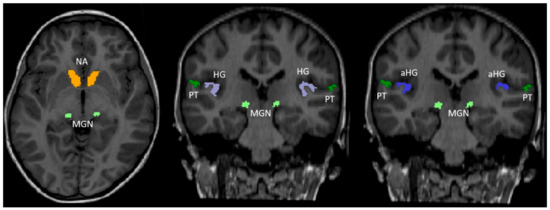

| Heschl’s gyrus (%) | GJB2 | 0.09(0.02) | 0.09(0.02) |

| Controls | 0.075(0.02) | 0.1(0.02) | |

| p-value | 0.09 | 0.02 | |

| Anterior Heschl’s gyrus (%) | GJB2 | N/A | 0.08(0.02) |

| Controls | N/A | 0.1(0.02) | |

| p-value | N/A | 0.0055 | |

| Planum temporale (%) | GJB2 | N/A | 0.14(0.05) |

| Controls | N/A | 0.15(0.05) | |

| p-value | N/A | 0.2 | |

| MGN (%) | GJB2 | N/A | 0.008(0.002) |

| Controls | N/A | 0.009(0.002) | |

| p-value | N/A | 0.11 | |

| Nucleus accumbens (%) | GJB2 | 0.03(0.01) | 0.05(0.01) |

| Controls | 0.03(0.01) | 0.05(0.01) | |

| p-value | 0.2 | 0.2 |